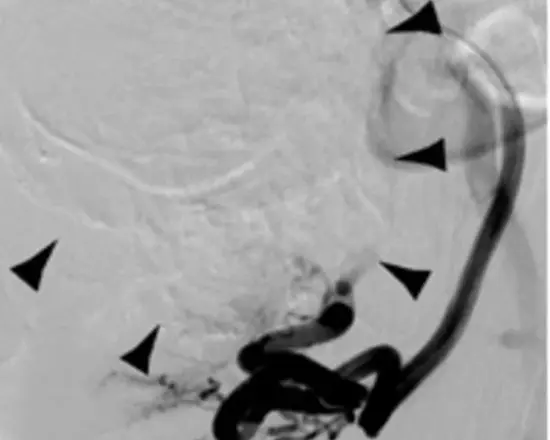

Bei der Myomembolisation führt der Radiologe einen dünnen Katheter durch einen kleinen Schnitt in der Leiste in die Beinarterie ein. Von hier aus wird der Katheter bis in die Arterien vorgeschoben, die die Gebärmutter versorgen. Zunächst wird Kontrastmittel gespritzt, so dass Blutgefäße, Gebärmutter und die umliegenden Organe auf dem Röntgenmonitor sichtbar werden. Anschließend werden kleine Kügelchen über den Katheter eingespritzt. Die Kügelchen verstopfen die Blutgefäße, die die Myome versorgen, wodurch das Myom zugrunde geht.